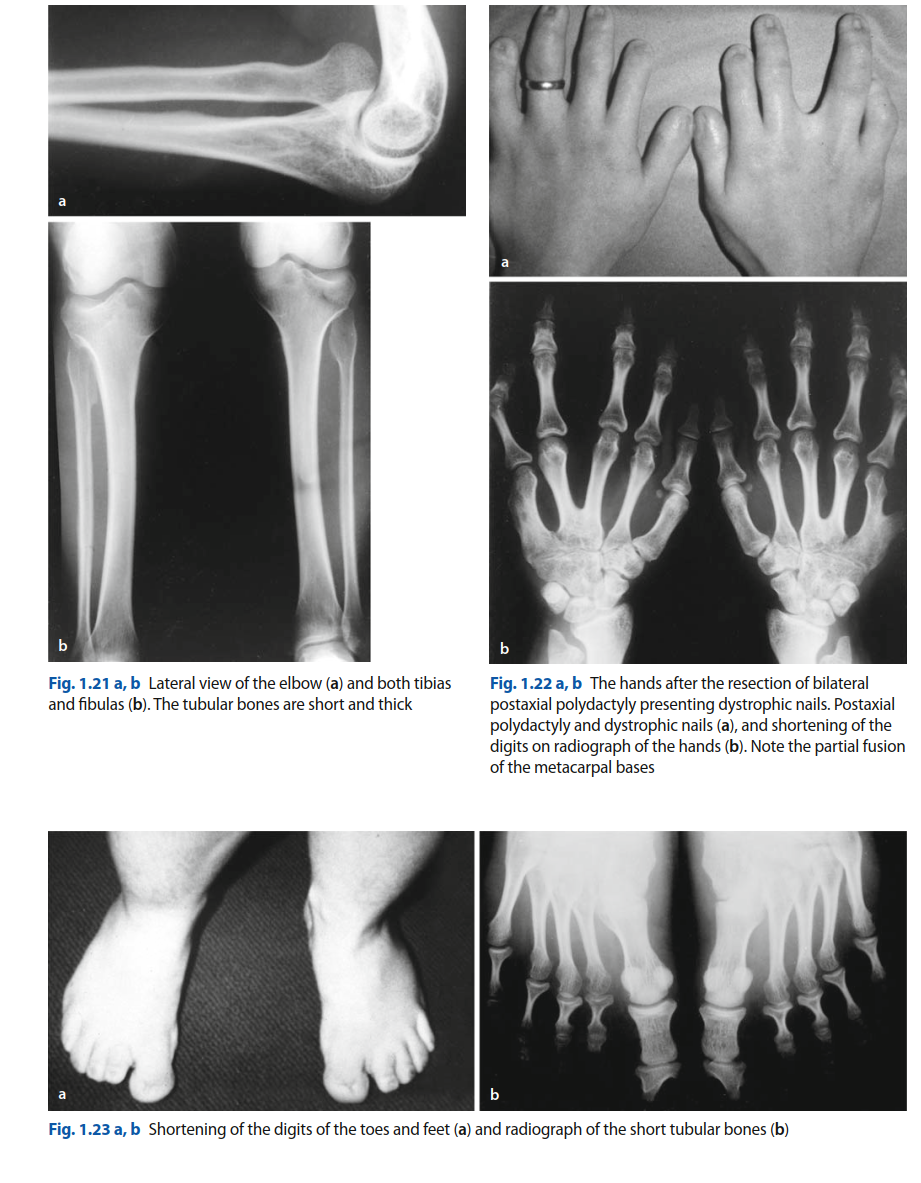

- تعدد الأصابع بعد المحور (Postaxial Polydactyly): وهي علامة مميزة جدًا للمتلازمة، حيث يولد الطفل بإصبع إضافي في اليدين (غالبًا في الجانب الزندي، أي بجانب الإصبع الصغير) والقدمين. يمكن أن يكون الإصبع الإضافي مجرد زائدة جلدية صغيرة أو إصبعًا كامل التكوين مع عظام وأوعية دموية وأعصاب خاصة به. يؤثر وجود هذا الإصبع على وظيفة اليد ومسك الأشياء وارتداء الأحذية.

- تشوهات الرسغ والقدم: قد يحدث اندماج بين بعض عظام الرسغ أو القدم، مما يحد من حركة هذه المفاصل.

- يقوم الطبيب بفحص الطفل بحثًا عن العلامات المميزة للمتلازمة، مثل قصر القامة، وتعدد الأصابع في اليدين والقدمين، وتشوهات الركبتين، والمظاهر الفموية مثل الأسنان الوليدية وتضخم اللثة.

- الأشعة السينية (X-rays): تُعد الأشعة السينية للعظام الطويلة واليدين والقدمين والحوض والعمود الفقري ضرورية لتحديد مدى التشوهات الهيكلية. تُظهر الأشعة السينية قصر العظام، وشكل الصفائح النموية، ووجود الأصابع الزائدة، وتشوهات المفاصل مثل خلع الورك أو الركبة الروحاء.

استئصال الأصابع الزائدة (Polydactyly Excision):

- عندما تؤثر الأصابع الإضافية على وظيفة اليد أو القدم (مثل صعوبة المسك أو ارتداء الأحذية).

- إذا كانت تسبب الألم أو الاحتكاك.

- لاعتبارات تجميلية، خاصة إذا كانت تؤثر على الجانب النفسي للطفل.